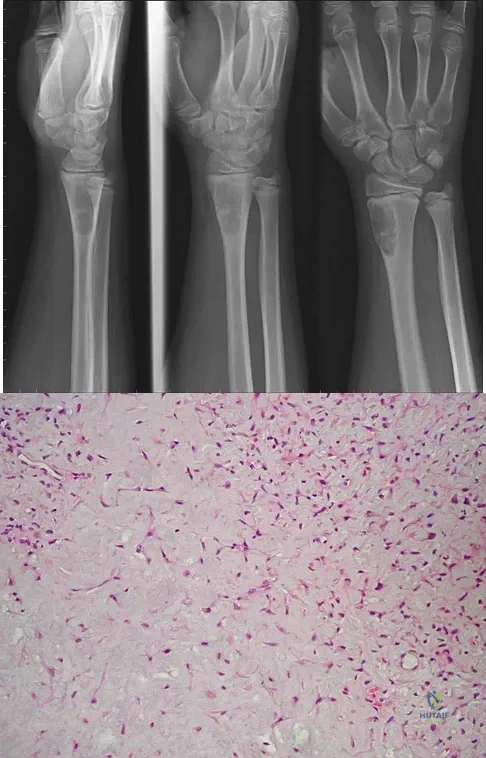

Question 67

A 14-year-old boy reports progressive right wrist pain. Radiographs are shown in Figure 3a, and a photomicrograph is shown in Figure 3b. What is the most likely diagnosis?

Explanation